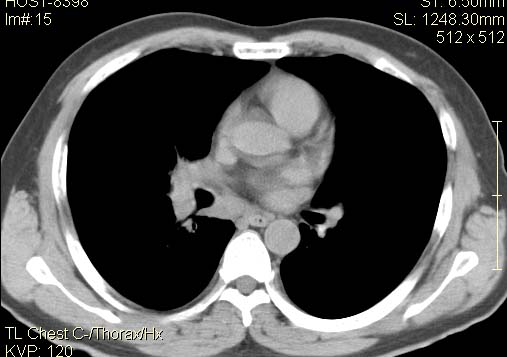

以下是引用qc80012345在2007-4-17 12:33:00的发言:[br]右肺下叶周围型肺癌伴肺门及纵隔内淋巴结转移;比较清楚。

以下是引用qingyuan在2007-4-17 14:19:00的发言:[br]右肺下叶外侧后段胸膜下区节结样病变、分叶、内可见空洞,壁厚薄不均,胸膜凹陷、肺门周围区纹理增粗、僵硬、并近似小结节样改变,肺门区软组织节结、纵膈淋巴结肿大,患者病史长、抗炎治疗无好转炎性改变基本排除,考虑:右肺下叶周围型肺癌伴纵膈及右肺门区淋巴结转移、肺内淋巴管受侵。